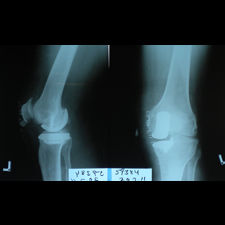

A 58 year old, male patient presented with a history of left knee pain and loss of function over 4 years.

On clinical and radiological examination, he was assessed as having Medial Compartment Osteoarthritis. A uni-compartmental knee replacement was recommended and performed in June 2011. Patient has gone onto complete recovery with a satisfactory clinical outcome. She returned to independent function, six weeks after the surgery and now has an pain-free existence with full function in the right knee after two months.